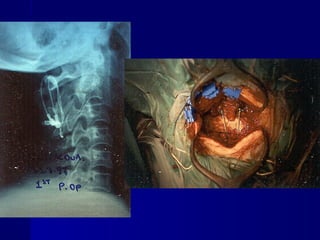

Injuries of tthhee uuppppeerr cceerrvviiccaall ssppiinnee

Μετεγχειρητικές ακτινογραφίες – 18mts